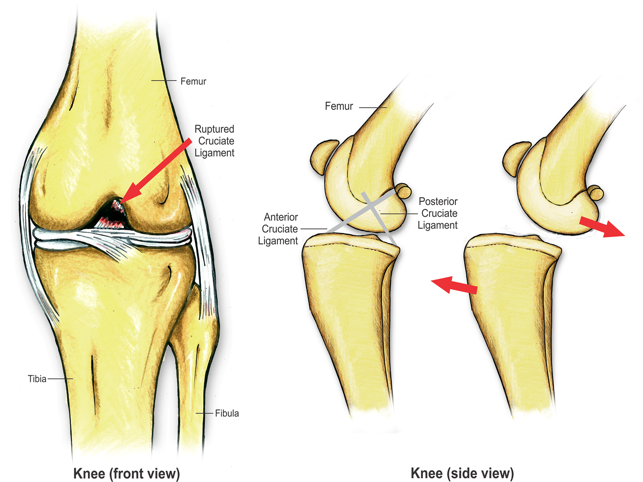

Increase value to your services

Are you still trying to explain a surgical procedure to your client using hand gestures or by stick drawings? Really? You want a client to say 'Yes' to a $3,000 TTA procedure with charades? With so much competition in the veterinary industry, you can't afford for a client to go for a second opinion or Dr Google themselves out of the procedure altogether. The iConsult will effectively and professionally help you educate your clients. There will be no need for Dr Google or second opinions.